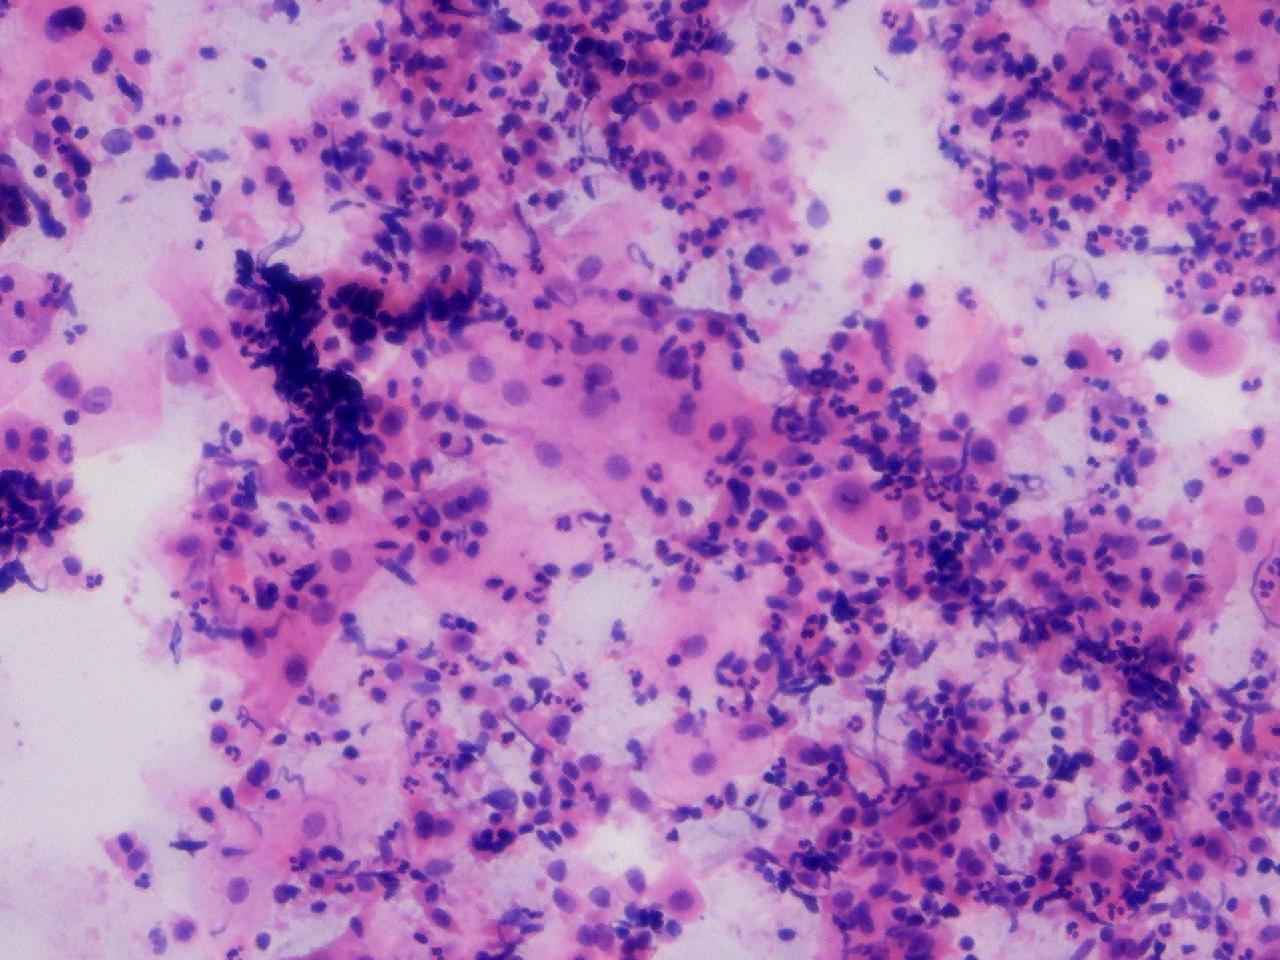

可见较多腺细胞。请教诊断。

性别

女

年龄

55岁

一般病史

绝经2年余,阴道淡血水3月余,子宫肌瘤10余年,HPV不详。

标本类型

妇科TCT

制片方法

离心后,沉降式制片

染色方法

图1

NILM